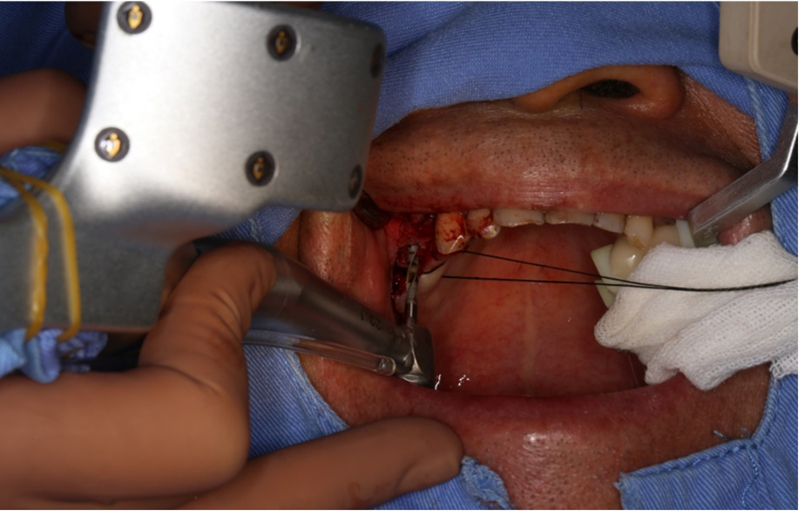

®完成標定及配準

®按照術前方案進行備洞及植體植入

®按照術前方案進行備洞及植體植入,醫(yī)生可以通過屏幕軟件引導對手術中植入點、角度、深度實時追蹤

®對植體深度及方向進行確認

®完成3顆植體的植入,植體位點如術前方案設計,均在同軸線。